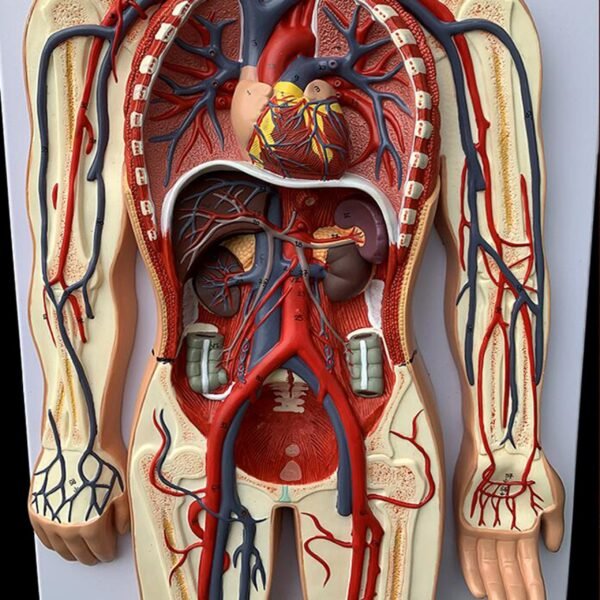

Blood Circulatory System model

* The model shows the main arteries and veins of the systemic blood circulation, with a total of 81 indications.